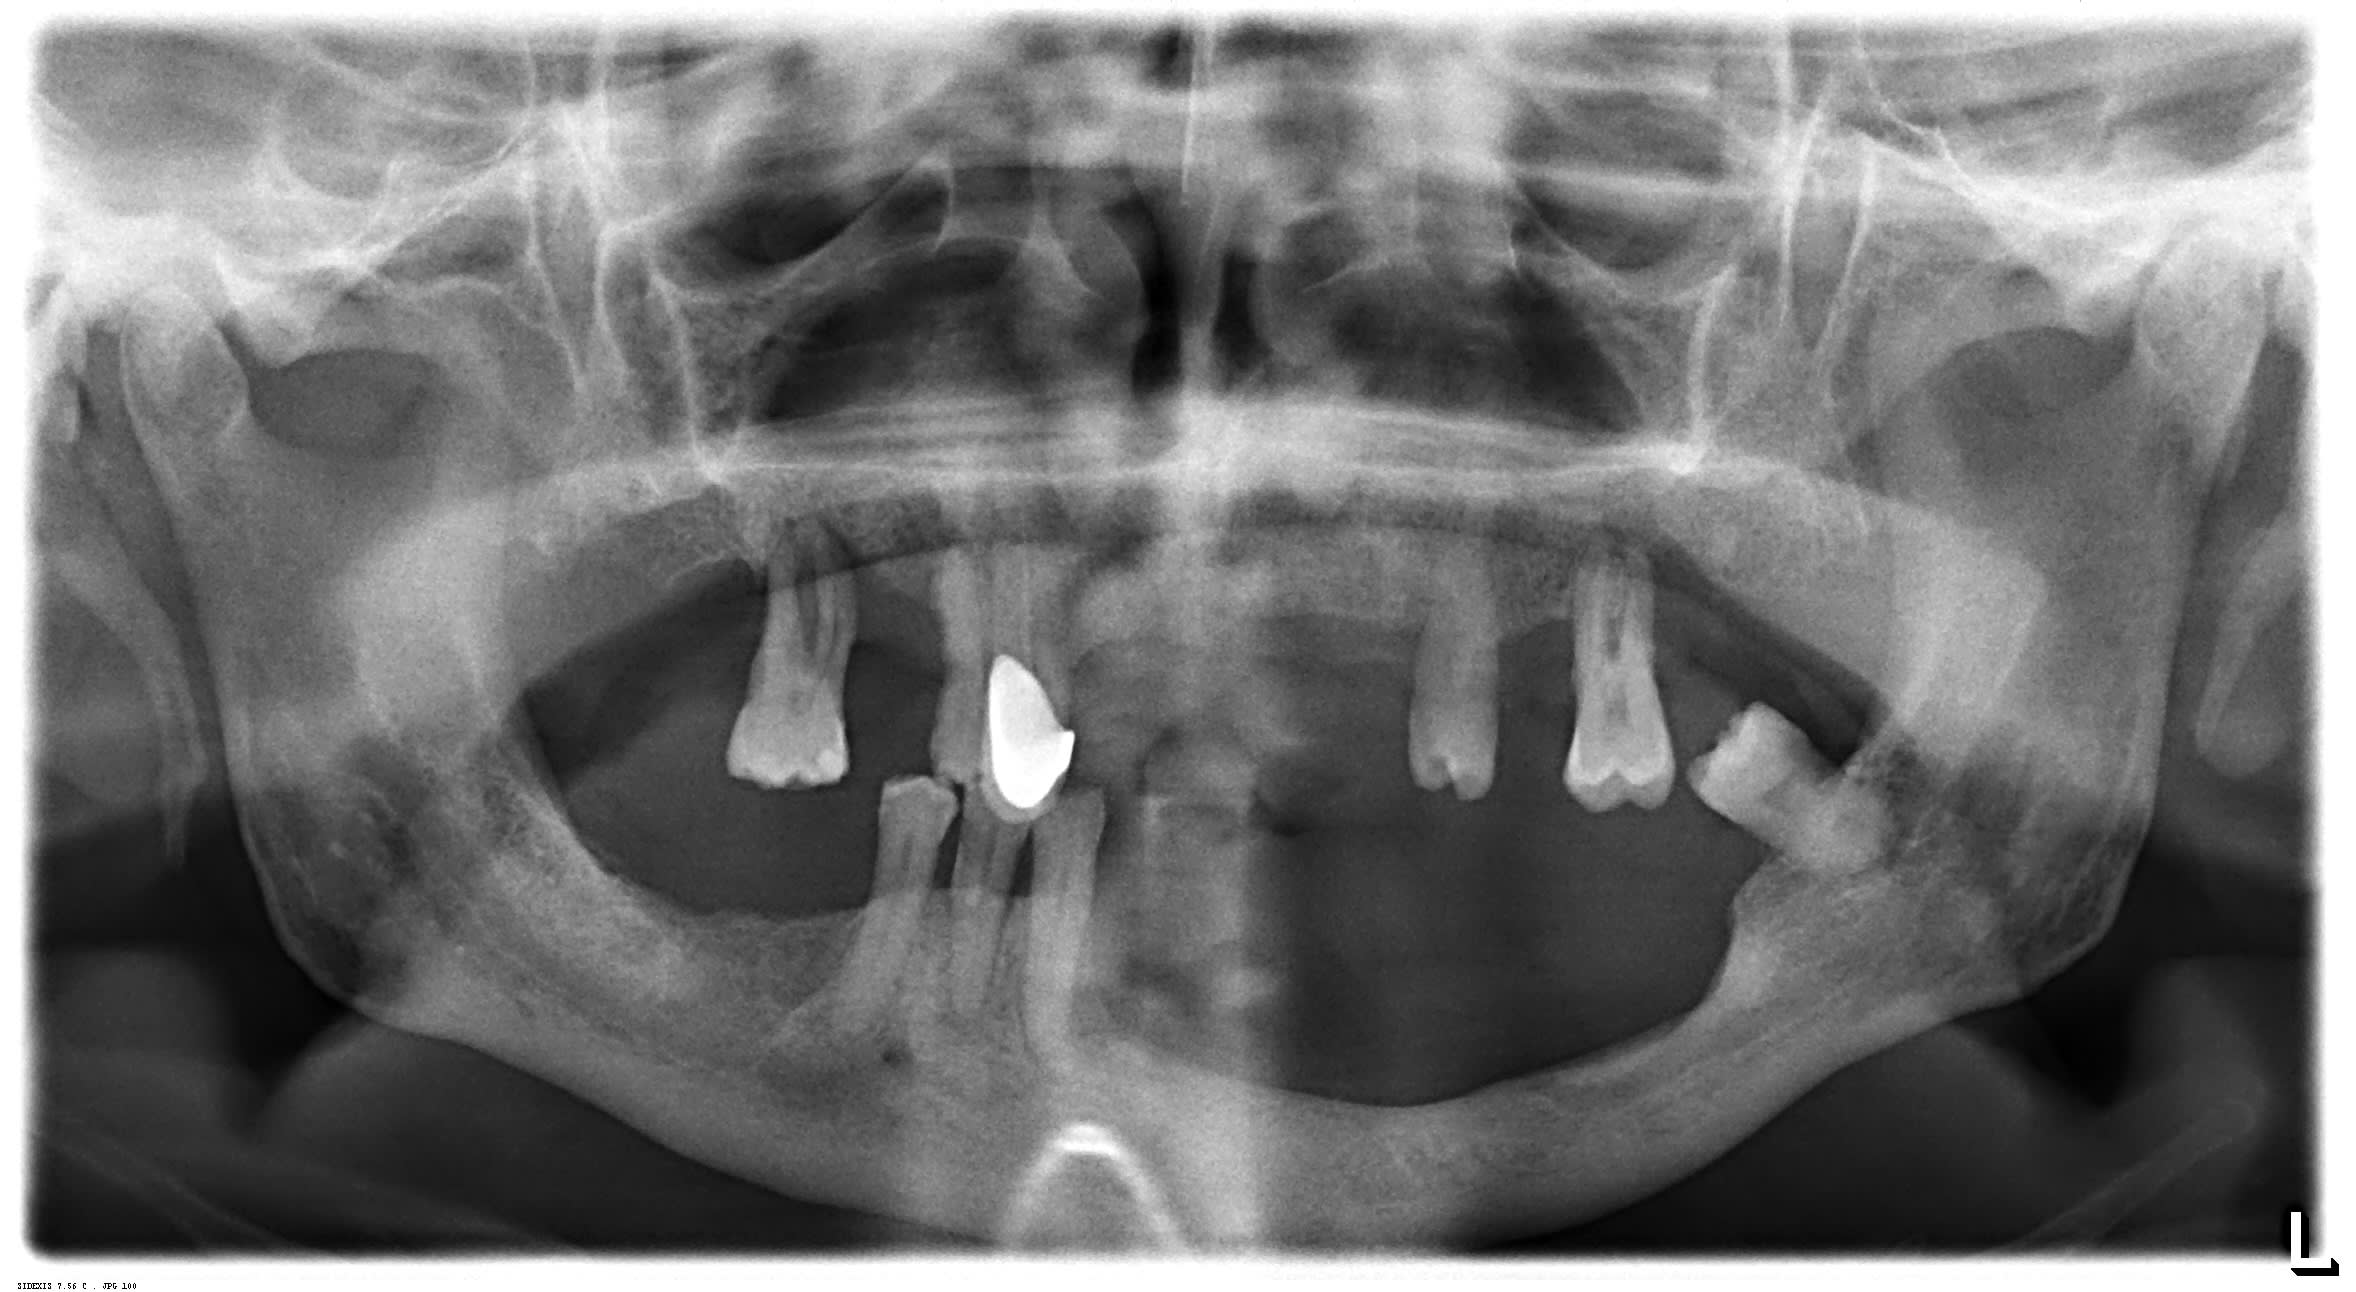

je me permets de poster pour vous demander quelles sont les solutions envisageables pour une reconstitution prothétique pour ce patient qui a été opéré il y a deux ans de ça à la mandibule secteur 30 pour un carcinome epidermoïde.

comment gérer les éventuelles douleurs au niveau de trou mentonnier, si les conditions anatomiques, et s'il n'a pas eu de rayons, est-il possible de lui poser des implants pour locators.

Je partirai sur un partiel resine avec une assise souple et surtout une bonne equilibration pour ne pas decapsuler les dents restantes.

Trouve un bon maxillo-facial, ne pense meme pas a poser des implants, c'est ingerable en l'etat.

Au vu de l' état du maxillaire, j'espère qu'il n'y a pas eu de rayons !!!!!Sinon les exos vont être Coton!

En bas partiel , moi je ferai une selle métal pour la rigidité et la meilleure fixation sur les dents restantes mais , comme Zorba, bonne épaisseur de résine souple pour ménager au mieux l'émergence du nerf